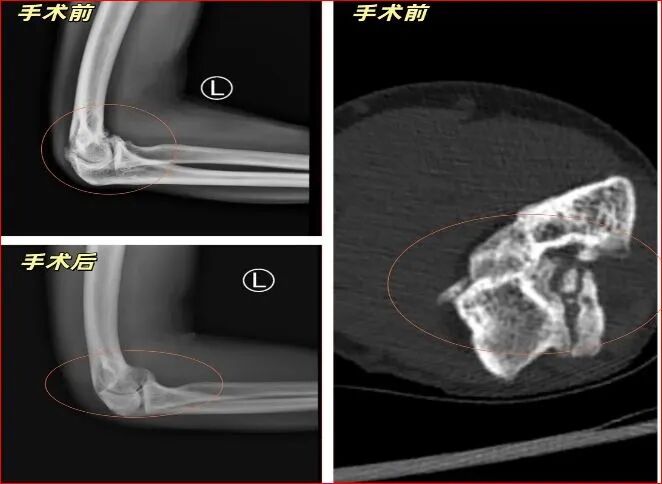

今年55岁的王先生,八年前因外伤导致左肘关节反复疼痛不适。一年前加重,肘关节周围异位骨化形成导致肘关节僵硬,他的左肘仿佛被时间锈住,严重影响其日常工作和生活。

术中,镜下景象令人触目惊心:王先生肘关节内及周围大量炎性滑膜增生,有1颗大小约0.5*1.5cm软骨样游离体存留,尺骨鹰嘴骨质增生,关节间隙变窄。

术中予以清理关节腔,切除增生滑膜,探查并取出游离体,尺骨鹰嘴增生骨质打磨修整成形,松解周围组织粘连……

手术非常顺利,极大地改善了关节功能,缓解了疼痛。术后,王先生的手臂,终于缓缓伸直,那双曾经连提起水杯都颤抖的手,再次触摸到生活的温度。